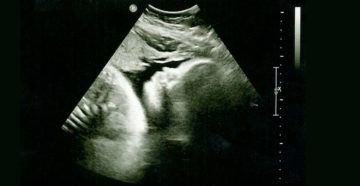

Показатели нормы на УЗИ на 34 неделе беременности: фото плода УЗИ – безопасный и достаточно…

32-я неделя беременности На 32 неделе беременности развитие плода продолжается в соответствии с заданной программой….